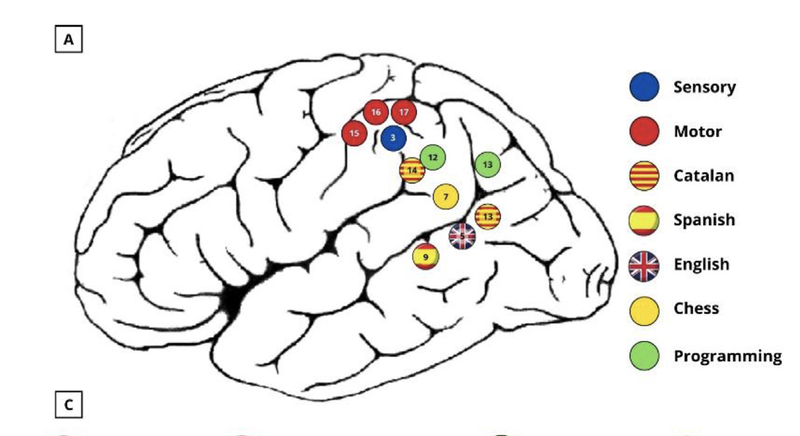

The gist of ESM is that because neural activity is electrical in nature, you can attempt to understand what the neurons in a particular part of the cortex do by manipulating the electrical signals in that area yourself to see what happens. Specifically, one can place an electrode in part of the brain that you're interested in and inject current there to see either what the patient experiences when you do this, or to see what activities you disrupt by altering the electrical activity there. I don't think I have the space for a full history lesson or anything, but suffice it to say that some of the earliest studies using this technique helped establish the layout of motor and somatosensory cortex by eliciting specific movements (e.g. isolated limb motions) or localized sensations (a feeling of pressure on part of the arm, e.g.) as the stimulation site was moved across the cortical surface. Critically, it's possible to carry out this procedure on an awake patient who is about to undergo brain surgery - after exposing the part of the brain you need to work with, you can begin stimulating and testing the patient behaviorally to understand where eloquent cortex is and isn't relative to different tasks. This is exactly what AB's surgeons did before resecting his tumor - what nearby parts of his left parietal lobe contributed to his bilingual language abilities? What about his programming skill? And of course, for our purposes, what about his chess playing? I've spared you the rather gory version of this figure in case some of you are a bit squeamish, but a schematic view of what they found is presented below.

Figure 8- (adapted from Cepero-Escribano et al., 2024) The results of ESM applied to Patient AB. Eloquent cortex supporting each of these abilities was found in the labeled regions near the surgical aperture, indicating how to try and preserve those abilities while still targeting his tumor.

Right there, labeled in yellow as site #7 - there is chess ability in Patient AB's brain. Stimulating there while he tries to carry out those behavioral tasks leads him to have serious difficulty, though stimulating at spots just adjacent has no such effect. That level of detail meant that his surgeons were able to define a surgical aperture around these various portions of eloquent cortex, remove the tumor, and (hopefully) preserve the skills that AB had developed over decades of experience and training. I say "hopefully" there, but at least with regard to the chess playing - it worked! Patient AB reported months after the surgery that he had been able to maintain his 1950 ELO rating after subsequent OTB play.